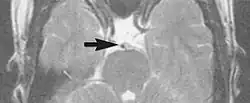

A motion artifact is one of the most common artifacts in MR imaging.[2] Motion can cause either ghost images or diffuse image noise in the phase-encoding direction. The reason for mainly affecting data sampling in the phase-encoding direction is the significant difference in the time of acquisition in the frequency- and phase-encoding directions.[1] Frequency-encoding sampling in all the rows of the matrix (128, 256 or 512) takes place during a single echo (milliseconds). Phase-encoded sampling takes several seconds, or even minutes, owing to the collection of all the k-space lines to enable Fourier analysis. Major physiological movements are of millisecond to seconds duration and thus too slow to affect frequency-encoded sampling, but they have a pronounced effect in the phase-encoding direction. Periodic movements such as cardiac movement and blood vessel or CSF pulsation cause ghost images, while non-periodic movement causes diffuse image noise (Fig. 1). Ghost image intensity increases with amplitude of movement and the signal intensity from the moving tissue. Several methods can be used to reduce motion artifacts, including patient immobilisation, cardiac and respiratory gating, signal suppression of the tissue causing the artifact, choosing the shorter dimension of the matrix as the phase-encoding direction, view-ordering or phase-reordering methods and swapping phase and frequency-encoding directions to move the artifact out of the field of interest.[1]